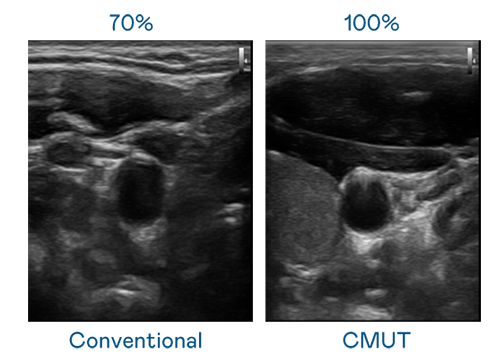

LEYU官網(wǎng)運(yùn)用 TFT 陣列 (Array) 制程延伸尖端感測(cè)技術(shù),開發(fā)出多種感測(cè)元件的LEYU官網(wǎng)。高解析度、品質(zhì)穩(wěn)定且可量產(chǎn)的 CMUT 元件,可制作高解析度超音波探頭、貼片型探頭,對(duì)病患實(shí)施精準(zhǔn)檢測(cè)與長時(shí)間生理監(jiān)測(cè)。